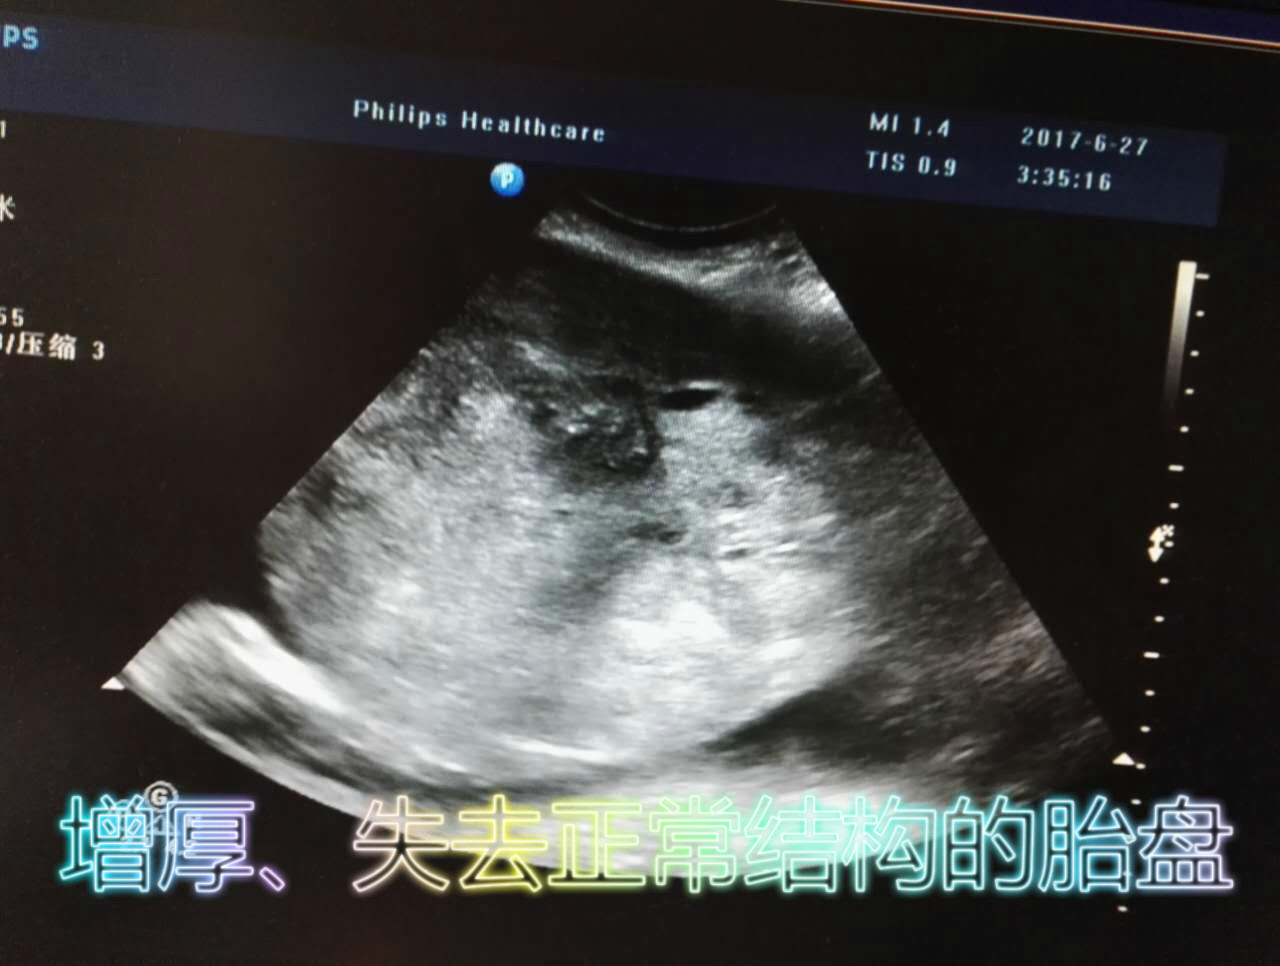

刘女士,孕32周+,因血压高、腹痛、流血来诊,产科医生查体,未听到胎心,遂到超声室确诊。我科B超医生紧急开通绿色通道,优先安排,在扫查到胎儿无胎心搏动后,把重心转移到胎盘上,胎盘位置正常,表现为增厚,厚约7.3cm,内回声杂乱不均质,彩色多普勒血流成像示:未见明显血流信号,最后诊断为死胎、胎盘早剥。无独有偶,孕34周+的卫女士,也因腹痛,夜间来急诊,诊断为胎盘早剥合并死胎。

这两例胎盘早剥均表现为胎盘大面积增厚,超过5cm,形态不规则,胎盘失去正常回声结构,大部剥离,出现不良结局,胎心均已消失。胎盘早剥是妊娠晚期发生的一种危急重症,多致严重的产前和(或)产后出血,危及母儿生命。其典型症状为突发持续性腹痛,伴或不伴阴道流血,危重者可出现休克,弥漫性血管内凝血(DIC)等。预防胎盘早剥要加强产前检查、检测血压、积极治疗妊高症,孕晚期避免长时间平躺、碰撞、摔倒等腹部外伤,一旦发现应立即终止妊娠。